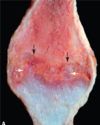

this is from a puppy. what is the arrow pointing to and why is it significant?

it is pointing to an area where the growth plate of the radius dissapeared, so no further growth can occur at this site. this likely happened because of some trauma to the radial growth plate in that location